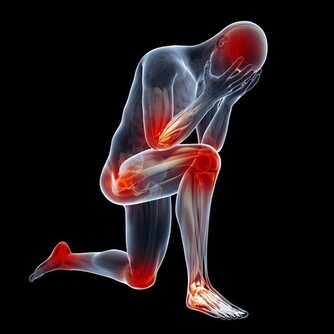

早衰,健忘失眠,食欲不振,骨骼與關節疼痛,腰膝酸軟,不耐疲勞,乏力,視力減退,聽力衰減。